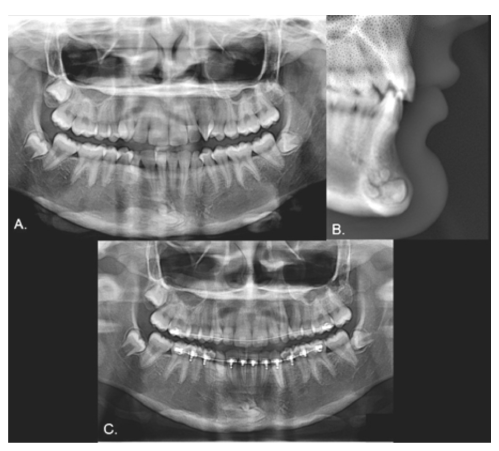

Case 1

Male, 12 years old. Clinical examination revealed that the inferior left canine was the only primary tooth still present (Fig. 1). The panoramic radiograph showed that the 3.3 was in a type 1 transmigration (Fig. 2A). The cone beam computed tomography (CBCT) showed that the crown of the transmigrated canine was very close to the adjacent incisors’ roots (Figs. 2 B and C). Despite the recommendation for surgical removal or even orthodontic traction, the parents chose not to treat the transmigrated tooth and instead to follow up with periodic radiographs.